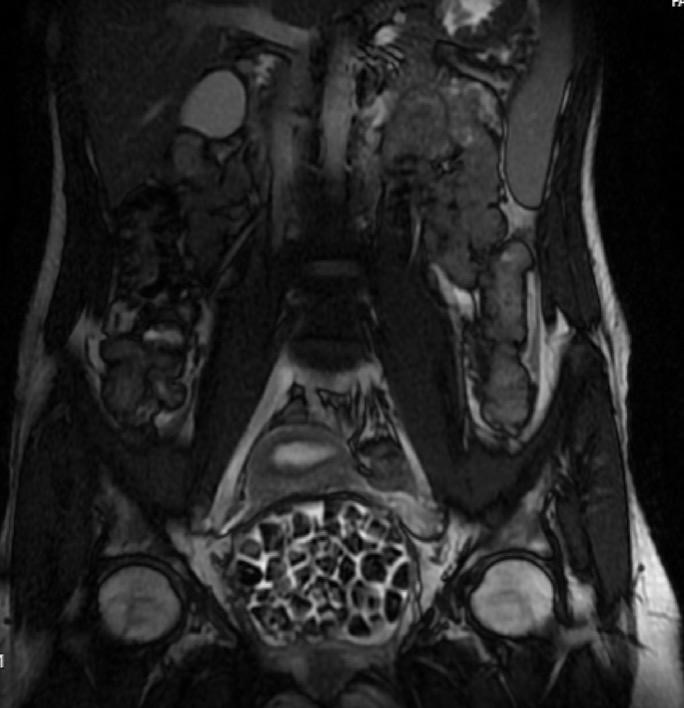

Hastasının durumuna yönelik konuşan Üroloji Uzmanı Doç. Dr. Erkan Erkan, "Hastamızın 2004 yılında doğduğunu ardından doğar doğmaz ekstrofi vezika dediğimiz 50 binde bir görülen bir anomaliden dolayı art arda ameliyatlar geçirdiğini öğrendik. 10 yaşında yine bir ameliyat geçirmişti, gerekli görüntüleme ve tetkiklerimizi yaptırdık. Normalde mesanesinin olması gereken yerin hemen arka kısmında taşlarla dolu bir kese olduğunu gördük, bunun üzerine ek görüntülemeler; MR çektirdik. Hastamız çelişkili açıklamalar almıştı, kendi radyolojik kliniğimiz ve edindiğimiz konsültasyonlarda taşların mesanede değil vajinal boşlukta oluştuğunu düşündük, bir planlama yaptık. Kadın doğum hocamızın da çabasıyla taşları tamamen temizledik ardından ileride normal bir hayat sürmesi bakımından oraya plastik cerrahi yaptık. 287 adet taş çıkardık, pratikte gerçekten görünce çok şaşırdık çünkü bu aynı zamanda literatürde çok nadir görülen bir olay. Biz ameliyata hazırlanırken de teorik olarak biraz araştırdık. Literatürde gördüğümüz kadarıyla buna benzer bu tanıma uyan bir vaka vardı. Literatürde sanırım yayınlanmış 2’nci vaka olacak. Farkındalık çok önemli, bilinçli bir hastamız vardı. Doğumsal anomaliyle doğan çocuklarımızda ileride bunlara bağlı bazı sıkıntılar çıkabileceğinin öngörülmesi lazım. İlgili tedavilerini alsalar bile düzenli takiplere gelmeleri gerekiyor. İleride eğer dikkat etmezse ki zannetmiyorum, tekrarlayabilir. Bu rahatsızlık ekstrofi vezikal epispadias durumu çok nadir bir durum" dedi.